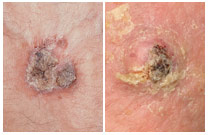

Basal Cell Carcinoma (BCC) Case Study

Inconvenient BCC, Good Outcome

Deborah S. Sarnoff, MD

A patient in his 40s with the genetic condition known as Gorlin syndrome had been treated for many basal cell carcinomas. During the COVID pandemic, he noticed a new bump on his upper lip. It didn’t seem serious to him, so, like many patients during that time, he did not see his dermatologist. When he finally did get checked, it was indeed a BCC and had grown deep enough to require several stages of Mohs surgery. The surgery eliminated the cancer but left the lower part of his face disfigured (top photo). Dr. Sarnoff’s business partner and husband, plastic surgeon Robert H. Gotkin, MD, was able to reconstruct the area with minimal scarring and an excellent cosmetic result (bottom photo, after healing). Read the full story here: https://skincancer.org/blog/we-dont-want-to-scare-you-but/